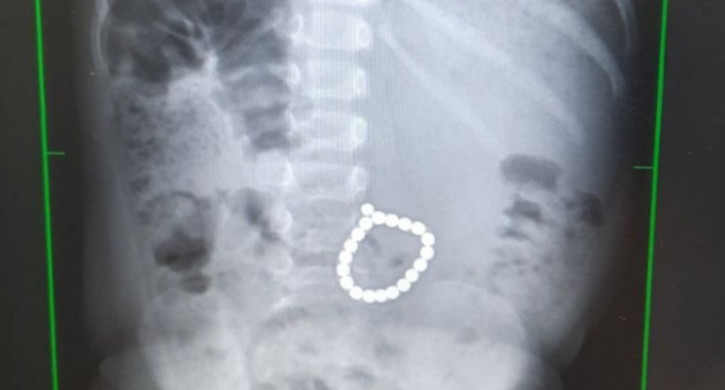

В прием отделении ребенка осмотрели хирурги, провели ренгенографию грудной клетки и брюшной полости. На снимке врачи обнаружили металлические округлые образования, сложенные в виде браслета.

«Ни обнаружить, ни извлечь магниты через небольшой лапаротомный разрез не удалось. Поэтому операционной бригаде пришлось перейти на открытую операцию – лапаратомию. И только тогда в начальном отделе тонкой кишки удалось обнаружить плотные образования. Вскрыли просвет тонкой кишки и нашли цепочку магнитиков», – рассказывает детский хирург  Николай Шеметов.

Магниты были связаны в браслет, поэтому они не расцепились и не попали в разные петли кишечника, что могло привести к множественным перфорациям кишечника и перитониту. Сейчас ребенок идет на поправку и чувствует себя хорошо.